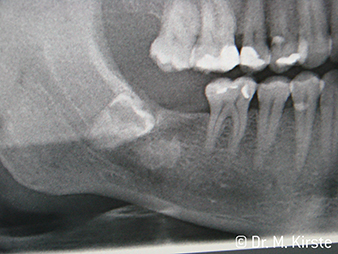

W&H Patientenbeispiel

Abbildung 7: ... wird mithilfe des neuen Winkelstücks elegant entfernt.